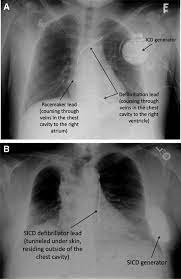

Sometimes, pacemaker and icd leads stop working properly due to damage or scar tissue accumulation. Pacemaker and icd troubleshooting, 2016. Like a pacemaker, an implantable cardioverter defibrillator, or icd, is a device placed under your skin. Implantable cardioverter defibrillators (icds) have a similar appearance to pacemakers. Implanting a pacemaker in your chest requires a surgical procedure. Temporary or permanent modification of the function (i.e., damage). Implantable cardiac conduction devices (also known as cardiac implantable electronic devices or cieds) are a very common medical device of the thorax cardiac pacemakers may be temporary or permanent, with the latter commonly known by the acronym ppm (permanent pacemaker). Pacemaker and icd manufacturers are arranged in alphabetical order with devices organized in numeric sequence.

Sometimes, pacemaker and icd leads stop working properly due to damage or scar tissue accumulation. An implantable cardioverter defibrillator (icd) looks similar to a pacemaker, though slightly larger. Which pacemaker/icd is that again. A pacemaker is a small device implanted in the chest. Pacemaker & icd are two different devices. Start studying pacemakers & icds. Movement and/or vibration of the pulse generator or leads. Die icd elektroden liegen regelrecht im rechten vorhof und im rechten ventrikel. Doctors also treat arrhythmias with implantable cardioverter defibrillators (icds). Icds are similar to pacemakers. Another type of pacemaker is called a biventricular pacemaker. Pacemaker and icd troubleshooting, 2016. Paces the heart muscles by providing an electrical.

Icd ( implantable cardiac defibrillator) on the other hand senses a very fast or chaotic rhythm, known as ventricular fibrillation, and gives an electrical. Devices that may interfere with icds and pacemakers. Pacemakers are classified by the nature of their pacing mode. Pertinent factors relating to each manufacturer's devices are referenced according to: 37.71 initial insertion of transvenous lead (electrode) into ventricle 02hk3jz insertion of pacemaker lead into right ventricle, percutaneous approach 37.72 initial insertion of transvenous leads (electrodes). Many devices combine a pacemaker and icd in one unit for people who need both functions. It also contains a computer that tracks your national heart, lung, and blood institute: Pacemaker and icd troubleshooting, 2016.

Implanting a pacemaker in your chest requires a surgical procedure. Pacemaker and icd troubleshooting, 2016. How does a pacemaker work? It also contains a computer that tracks your national heart, lung, and blood institute: Another type of pacemaker is called a biventricular pacemaker. An implantable cardioverter defibrillator (icd) looks similar to a pacemaker, though slightly larger. Once the wires are in place, your doctor will make a small cut into the. Temporary or permanent modification of the function (i.e., damage). ©2021 daily search trends feedback. Pertinent factors relating to each manufacturer's devices are referenced according to: Devices that may interfere with icds and pacemakers. It works very much like a pacemaker. While pacemaker's job is to treat slow heart rate, icd's job is to treat very fast chaotic heart rhythm.